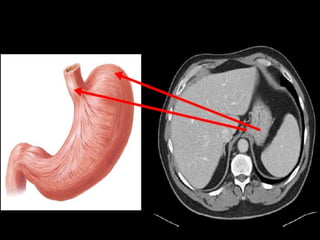

Stomach:

 has a lesser curvature, which is connected to the porta hepatis

of the liver by the lesser omentum, and a greater curvature

from which the greater omentum is suspended.

 The cardiac region receives the esophagus.

 The dome-shaped upper portion of the stomach, which is

normally filled with air, is the fundus.

 The main center portion of the stomach is the body.

 The pyloric portion of the stomach has a thick muscular wall

and a narrow lumen that leads to the duodenum.

3/22/2024 44

CT cross sectional

anatomy.